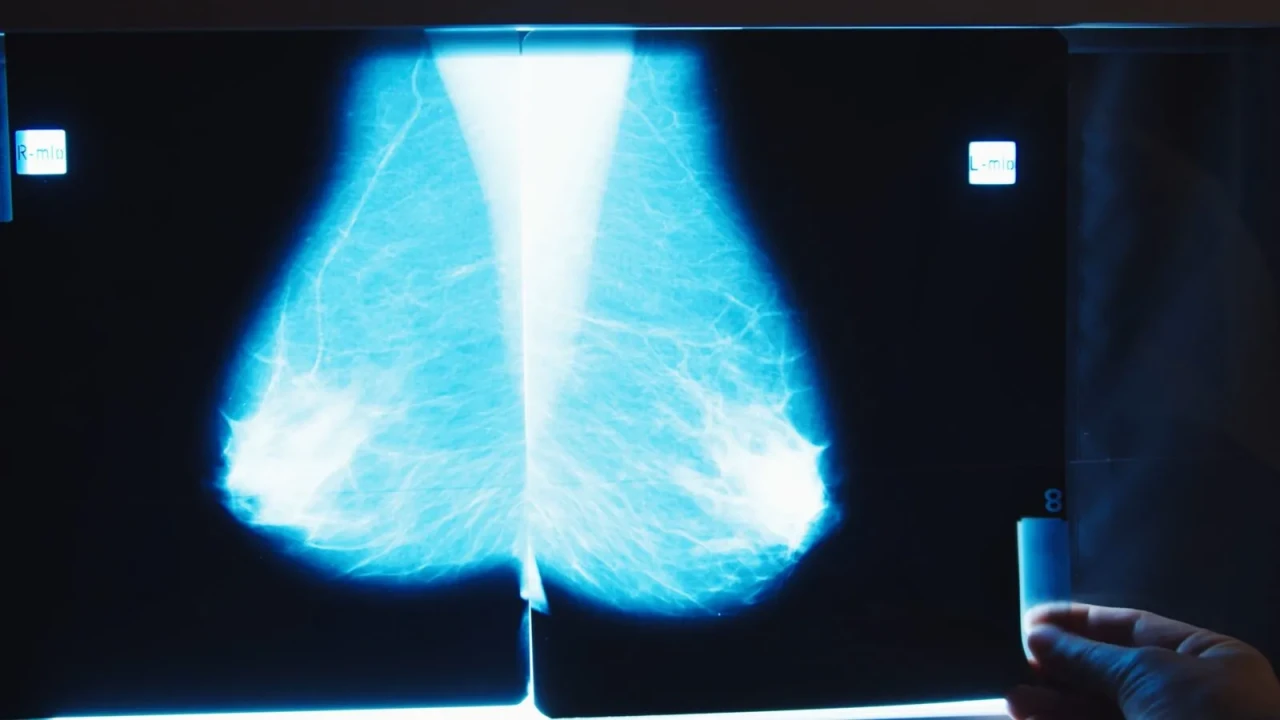

Yeni Birlik Gazetesi Sağlık Yeni mamografi teknolojileri umut vadediyor; ancak uzmanlar henüz ikna olmadı

Yeni mamografi teknolojileri umut vadediyor; ancak uzmanlar henüz ikna olmadı

Dijitalleşmenin ve yapay zekâ teknolojilerinin sağlık alanına etkisi büyüyor. Son yıllarda geliştirilen yapay zekâ tabanlı mamografi tarama sistemleri, meme kanserinin erken teşhisinde devrim yaratma potansiyeli taşıyor. Ancak bu teknolojilerin yaygın olarak benimsenmesinin önünde büyük bir engel var: güven eksikliği.

ABD merkezli sağlık ve bilim haber platformu STAT, 29 Mayıs 2025 tarihli haberinde, birçok radyoloğun yapay zekâ ile çalışan mamografi tarama sistemlerine mesafeli yaklaştığını ortaya koydu. Bunun başlıca nedeni, bu sistemlerin gerçekten kanserden ölüm oranlarını düşürüp düşürmediği konusundaki sınırlı bilimsel kanıtlar.

Radyologlar, yapay zekâ algoritmalarının bazı tümörleri yakalamada etkili olabileceğini kabul etse de, yanlış pozitif oranlarının artabileceği ve bu durumun gereksiz biyopsilere neden olabileceği endişesi taşıyor. Ayrıca, bazı sistemlerin şeffaf olmaması ve kararlarının açıklanabilir olmaması da uzmanların teknolojiye duyduğu güveni sarsıyor.

FDA Onaylı, Ama Yine de Soru İşaretleri Var

Birçok yapay zekâ destekli mamografi aracı FDA tarafından onaylanmış olsa da, bu onaylar genellikle teknolojinin güvenli kullanımıyla ilgili sınırlı testlere dayanıyor. Oysa radyologlar, daha kapsamlı klinik deneyler ve uzun vadeli sağlık sonuçlarına dair veriler görmek istiyor. Başka bir ifadeyle; yapay zekâ, doğru sonuçlar verebilir ama bu sonuçların hasta yaşamını ne ölçüde iyileştirdiği henüz net değil.

Hasta Güvenliği ve Etik Kaygılar Öne Çıkıyor

Yapay zekânın karar mekanizmasının tamamen otomatikleşmesi, bazı sağlık profesyonelleri için endişe kaynağı. İnsan gözetimi olmadan yapılan analizlerin etik açıdan tartışmalı olduğu vurgulanıyor. Ayrıca, sistemin eğitildiği veri setlerinin çeşitliliği de bir diğer tartışma konusu. Örneğin, farklı etnik gruplardan gelen veriler yeterince temsil edilmediyse, algoritmanın performansı eşitlikçi olmayabilir.

Gelecek Ne Vaat Ediyor?

Her ne kadar şu an için güven sorunu gündemde olsa da, yapay zekânın sağlık alanında devrim yaratacağı bir gerçek. Uzmanlar, daha şeffaf ve klinik olarak test edilmiş sistemlerin geliştirilmesiyle bu güven açığının kapanabileceğini belirtiyor. Ancak bu sürecin zaman alacağı ve eğitimli insan gözüyle teknolojinin entegrasyonunun kaçınılmaz olduğu da vurgulanıyor.

Kaynak: Statnews